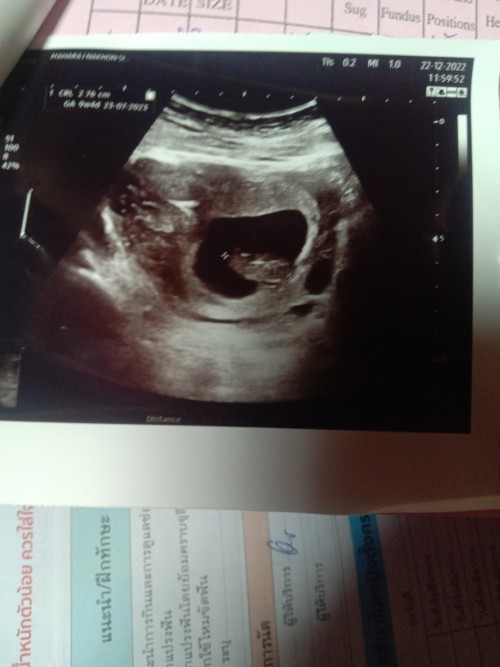

อันนี้คือรูปซาวตอน9วีค3วันหมอบอกว่ายังไม่เจอตัวเจอเเค่ถุงไข่เเดง อยากทราบว่าเเม่ๆซาวเจอตัวน้องตอนกี่วีคคะ